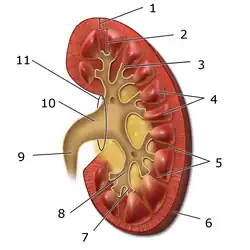

Aparato urinario

Es un conjunto de órganos encargados de la producción, almacenamiento y expulsión de la orina. Está formado por dos riñones, dos uréteres, la vejiga urinaria y la uretra.